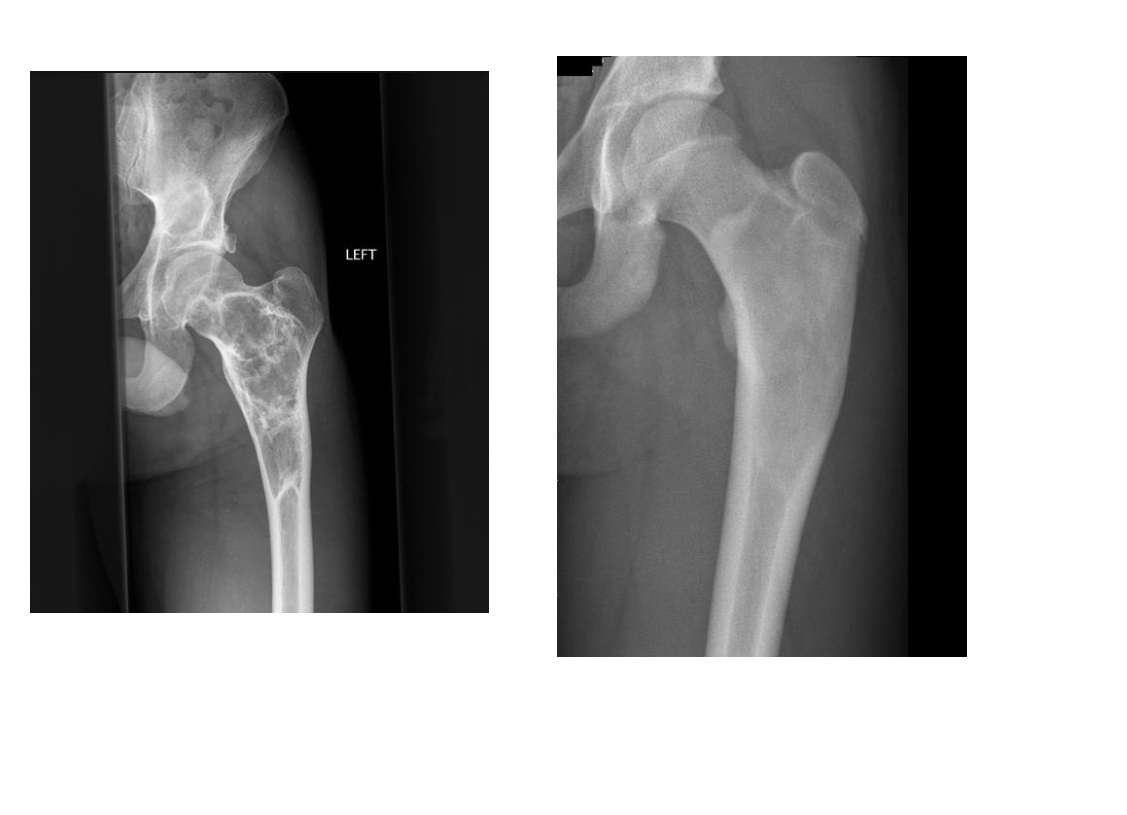

Chondrosarcoma

May be cecondary to

- Osteochondromas

- enchondromas

Chondrosarcomas occur in the pelvis, femur, humerus.

Skull base, TMJ

DDX

-Most well differentiated, low grade = ‘low grade chondroid lesion’ , cant differentate from enchondroma

-Bone infarct

MRI

Lobular growth

High 2 signal/STIR, low T1

ring and arcs/chondroid matrix islands on CT

Soft tissue extension

**endosteal scalloping. **

if no mineralized matrix/rings and arcs = aggressive/high grade

How to tell chondrosarcoma from enchondroma ?

* Pathological fracture occurring with minimal trauma

* Multilayered or spiculate periosteal reaction

* Permeative or moth-eaten osteolysis

* Cortical destruction

* A soft tissue mass

Endosteal scalloping more than 2/3 cortex